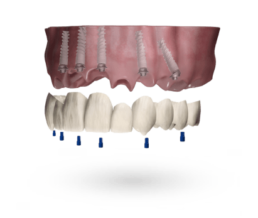

W przypadku stomatologii widoczny jest np. trend odchodzenia od tradycyjnych protez, które w świadomości seniorów wymagają dużej ilości pracy nad ich utrzymaniem w należytej higienie, a jednocześnie – nie zapewniają pełni swobody funkcjonowania tak, jak ma to miejsce w przypadku implantów dentystycznych. Srebrni pacjenci coraz częściej, i coraz powszechniej korzystają z dostępu do Internetu, by samodzielnie odnajdywać informacje o dostępnych metodach leczenia, uniezależniając się od wsparcia krewnych w tym względzie. Jaki wpływ będą mieli ci nowi-srebrni pacjenci na rynek stomatologii? Według Raportu Fortune Business Insights światowy rynek implantów dentystycznych osiągnie wartość 5,81 miliarda USD do 2027 roku, m.in. właśnie dzięki tej stale rosnącej grupie pacjentów.

„Polacy stają się coraz bogatszym społeczeństwem, systematycznie zmniejszając dystans do Zachodu. Naturalnym jest zatem, że wraz ze wzrostem majątku, zaczynamy poszukiwać nowych rozwiązań. Rodzimego pacjenta będzie w coraz większym stopniu interesowało to, czy dana procedura może rozwiązać jego problemy całkowicie, nawet jeśli wiązałoby się to z poniesieniem wyższych kosztów.” – mówi Sławomir Polański, Key Account Manager w Alpha Bio Polska– „Jeszcze parę lat temu była to niezmiernie rzadka sytuacja – dziś i w przyszłości, stanie się powszechna. Bardzo dobrą ilustracją tego trendu jest dynamicznie rosnąca liczba prac pełnołukowych w polskich gabinetach.”